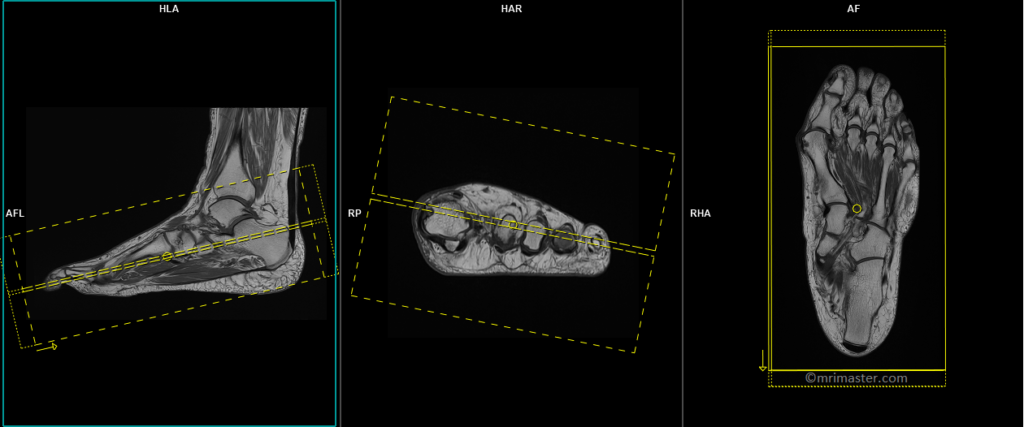

T1 tse axial 3 mm (coronal in anatomical position)

Plan the axial slices on the sagittal plane, angling the positioning block perpendicular to the metatarsal and phalanges bones. Check the positioning block in the other two planes. An appropriate angle must be given in the coronal plane (perpendicular to the metatarsal and phalanges bones). The slices must be sufficient to cover the foot from the tip of the toe up to the tarsal bones. Most of the radiologists refer this as an axial plane even though in anatomical position this is coronal plane

T2 stir axial 3 mm

Plan the axial slices on the sagittal plane, angling the positioning block perpendicular to the metatarsal and phalanges bones. Check the positioning block in the other two planes. An appropriate angle must be given in the coronal plane (perpendicular to the metatarsal and phalanges bones). The slices must be sufficient to cover the foot from the tip of the toe up to the tarsal bones.

T1 tse coronal 3mm

Plan the coronal slices on the sagittal plane, angling the position block parallel to the metatarsal and phalanges bones. Check the positioning block in the other two planes. An appropriate angle must be given in the axial plane, parallel to the line across the metatarsal bones. Slices must be sufficient to cover the foot from the plantar aspect up to the dorsal aspect. Most of the radiologists refer this as a coronal plane even though in anatomical position this is an axial plane.